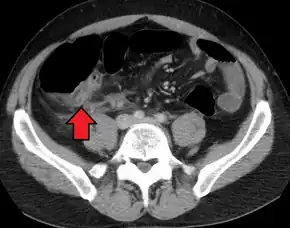

In children the clinical examination is important to determine which children with abdominal pain should receive immediate surgical consultation and which should receive diagnostic imaging.[42] Because of the health risks of exposing children to radiation, ultrasound is the preferred first choice with CT scan being a legitimate follow-up if the ultrasound is inconclusive.[43][44][45] CT scan is more accurate than ultrasound for the diagnosis of appendicitis in adults and adolescents. CT scan has a sensitivity of 94%, specificity of 95%. Ultrasonography had an overall sensitivity of 86%, a specificity of 81%.[46]

Abdominal ultrasonography, preferably with doppler sonography, is useful to detect appendicitis, especially in children. Ultrasound can show the free fluid collection in the right iliac fossa, along with a visible appendix with increased blood flow when using color Doppler, and noncompressibility of the appendix, as it is essentially walled-off abscess. Other secondary sonographic signs of acute appendicitis include the presence of echogenic mesenteric fat surrounding the appendix and the acoustic shadowing of an appendicolith.[47] In some cases (approximately 5%),[48] ultrasonography of the iliac fossa does not reveal any abnormalities despite the presence of appendicitis. This false-negative finding is especially true of early appendicitis before the appendix has become significantly distended. Also, false-negative findings are more common in adults where larger amounts of fat and bowel gas make visualizing the appendix technically difficult. Despite these limitations, sonographic imaging with experienced hands can often distinguish between appendicitis and other diseases with similar symptoms. Some of these conditions include inflammation of lymph nodes near the appendix or pain originating from other pelvic organs such as the ovaries or Fallopian tubes. Ultrasounds may be either done by the radiology department or by the emergency physician.[49]

Computed tomography

Where it is readily available, computed tomography (CT) has become frequently used, especially in people whose diagnosis is not obvious on history and physical examination. Although some concerns about interpretation are identified, a 2019 Cochrane review found that sensitivity and specificity of CT for the diagnosis of acute appendicitis in adults was high.[51] Concerns about radiation tend to limit use of CT in pregnant women and children, especially with the increasingly widespread usage of MRI.[52][53]

The accurate diagnosis of appendicitis is multi-tiered, with the size of the appendix having the strongest positive predictive value, while indirect features can either increase or decrease sensitivity and specificity. A size of over 6 mm is both 95% sensitive and specific for appendicitis.[54]

However, because the appendix can be filled with fecal material, causing intraluminal distention, this criterion has shown limited utility in more recent meta-analyses.[55] This is as opposed to ultrasound, in which the wall of the appendix can be more easily distinguished from intraluminal feces. In such scenarios, ancillary features such as increased wall enhancement as compared to adjacent bowel and inflammation of the surrounding fat, or fat stranding, can be supportive of the diagnosis. However, their absence does not preclude it. In severe cases with perforation, an adjacent phlegmon or abscess can be seen. Dense fluid layering in the pelvis can also result, related to either pus or enteric spillage. When patients are thin or younger, the relative absence of fat can make the appendix and surrounding fat stranding difficult to see.[55]